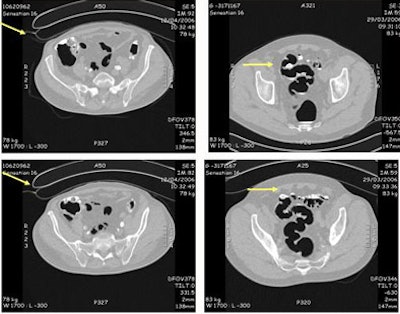

![]() |

| A sigmoid tumor, 5 x 2 cm in size, was detected at both VC and colonoscopy. The lesion was a well- to moderately differentiated transmural invasive adenocarcinoma classified as pT3N2Mx R0. Images courtesy of Dr. Didier Bielen. |

The combined VC and colonoscopy results were normal in 32 of 75 patients, and lesions 5 mm and smaller were found in 30 patients (VC detected 11/95). Four patients had polyps 6-7-mm in diameter (VC detected 3/8), two patients had polyps 8-9-mm in diameter (VC detected 4/5), six had polyps 10-mm or larger (VC detected 7/7), and one patient had a rectosigmoid tumor, also seen in both exams.